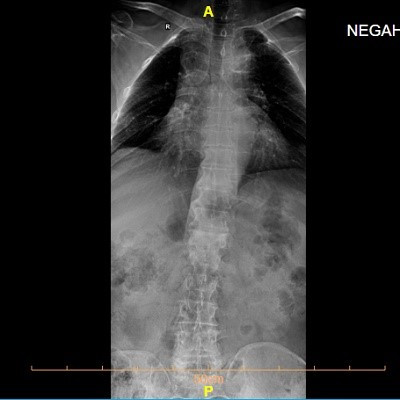

تشخیص اولیه اسکولیوز معمولا با معاینه بالینی انجام می شود. پزشک از بیمار می خواهد به جلو خم شود تا نامتقارنی شانه ها یا برجستگی پشت مشخص شود. برای تشخیص دقیق و تعیین شدت انحراف ، تصویر برداری با اشعه ایکس یا رادیولوژی ضروری است. میزان انحراف با زاویه ای به نام زاویه کاب اندازه گیری می شود. در برخی موارد ، برای بررسی دقیق تر ساختار ستون فقرات یا آسیب های عصبی ، از ام آر آی یا سی تی اسکن نیز استفاده می گردد.